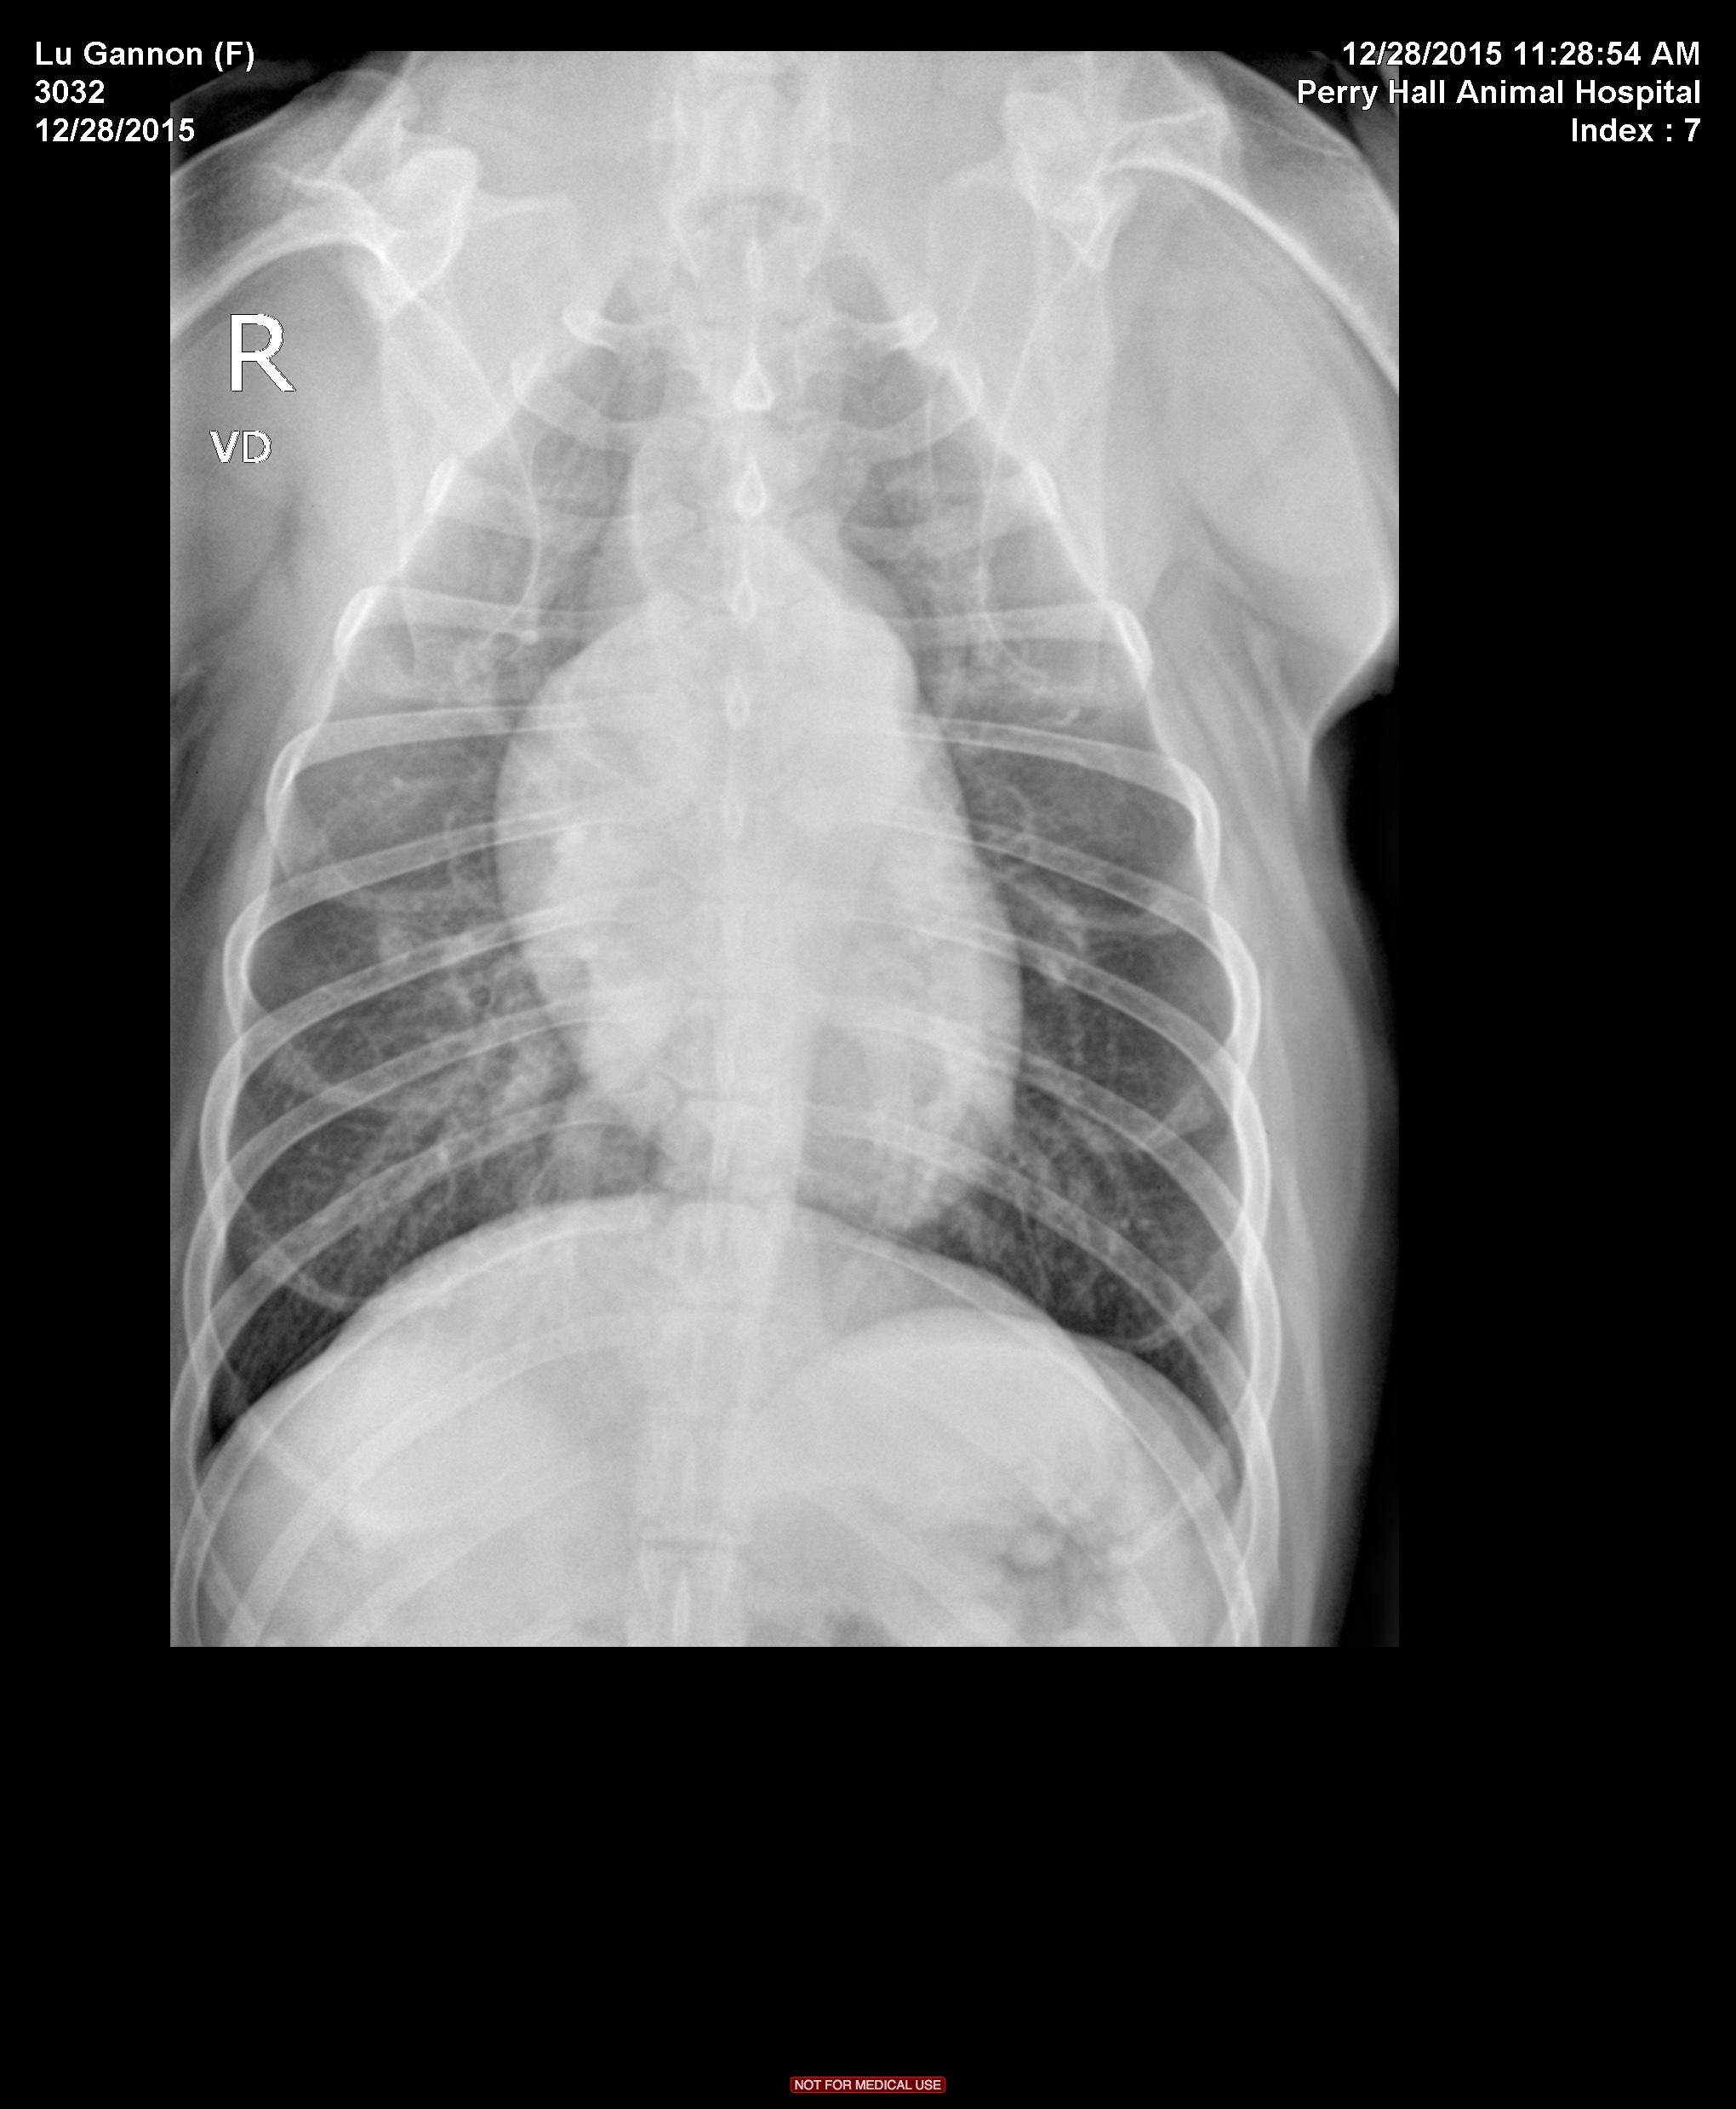

The patient is a 9 year old FS Pitbull with a 3 day history of lethargy and decreased appetite. Has not eaten in 24 hours, decreased water intake. Seems almost ataxic or weak to the owner at home, overall very depressed. Hx of allergies that are controlled.

Physical Exam: Depressed, Temp 101.9. MM pink/slightly tacky. cardiac wnl, lungs wnl on auscultation. BCS 5/9. No abdominal discomfort on palpation. Walking normally x 4 in room but is much less energetic than usual.